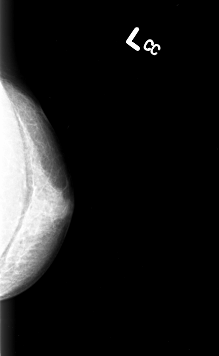

B_3003_1.LEFT_CC

LEFT_CC LINES 4264 PIXELS_PER_LINE 2624 BITS_PER_PIXEL 12 RESOLUTION 50 NON_OVERLAY